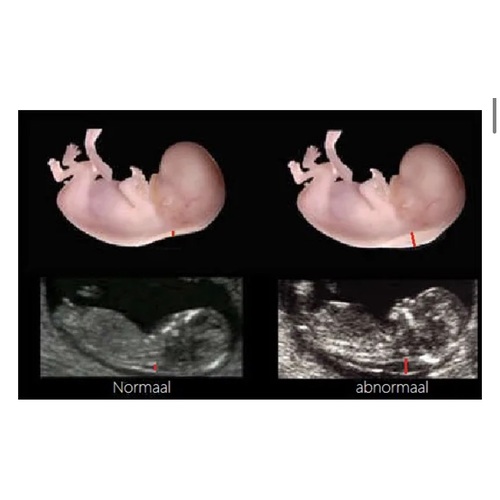

In België wordt dit standaard gemeten tijdens de termijnecho. Als de nekplooi te dik is, doen ze hier dan zelfs géén NIPT. Dit omdat die hier wordt terugbetaald en de kans op een afwijking dan sowieso al erg groot is. Dan wordt het meteen een vlokkentest of punctie. Valt de nekplooi binnen de normale waarden, dan kan je de NIPT laten doen. Omdat er jammer genoeg toch ook nog afwijkingen voorkomen ondanks een normale nekplooi. Het is niet zo dat als de nekplooi normaal is, er sowieso geen trisomie zou kunnen voorkomen.

He! De termijn echo is net iets te vroeg (9-11 weken) om afwijkingen te kunnen opsporen. Daarom wordt de combinatietest het liefst tussen 12-14 weken uitgevoerd. Soms wordt er wel een opvallend dikke nekplooi gezien bij de termijnecho, maar het is nog onduidelijk wat dat betekent. Daar wordt op het moment nog onderzoek naar gedaan. Als het wordt gezien, adviseren ze een nipt test. Als er geen dikke nekplooi bij de termijnecho wordt gezien, dan is dat geen garantie dat er geen downsyndroom is omdat dit ook pas later kan ontwikkelen.